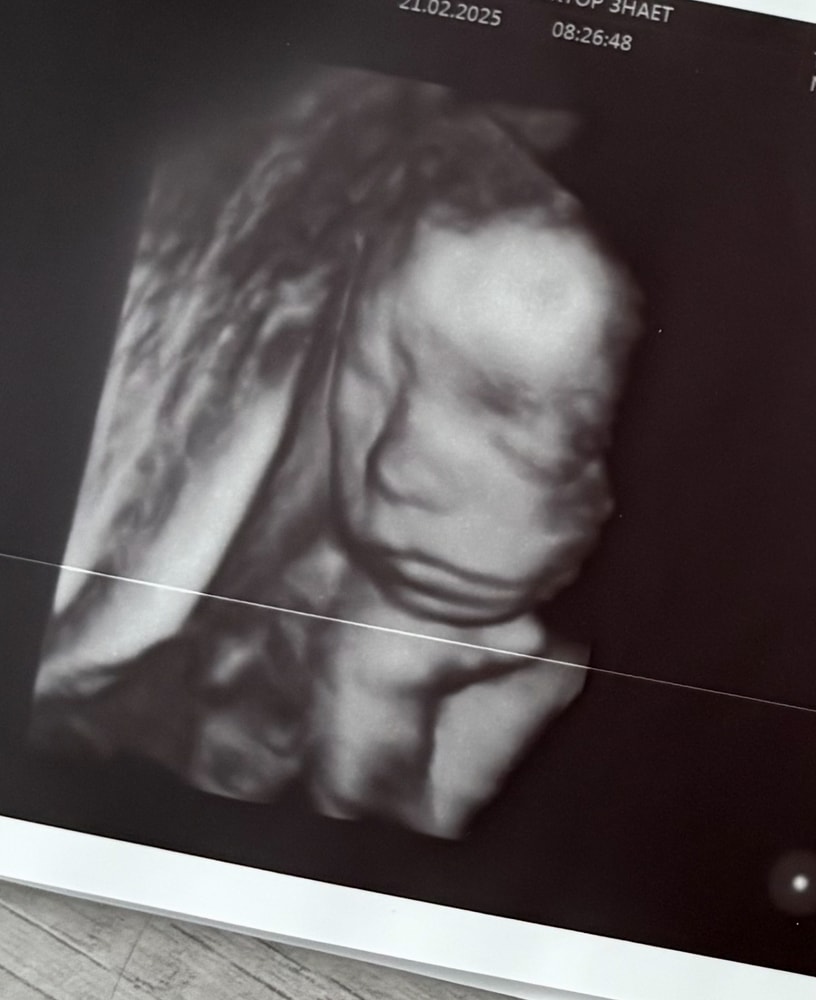

Tatiana, а зачем тогда пишут патологию, если могут написать, что не визуализируется? На хорошем оборудовании все очень четко видно, мне и стопы с пальчиками показали, и ладошки, и кулачки - можно сосчитать пальчики. Вот фотки 3д (делали просто для меня). Даже когда бесплатно делала, врач просила пойти погулять, поесть, чтоб малыш перевернулся, если не смогла что-то рассмотреть. В общем, странная история, слава богу все хорошо Изображение Изображение

Уютная, прикрепила ниже фото с узи.

Tatiana, вот где пальцы одной длины, это в Ставрополе делали на экспертнике, остальное Ростов, вот такие диагнозы мне ставили фото где все слиплось это в ПЦ смотрели, когда синдактилию поставили Последнее фото, узи за очень дорого в Ростове Я думаю, что давать оценку как видит врач не стоит, но в данном случае, я очень рада, что супер модный эксперт и спец в своем деле ошибся Изображение Изображение Изображение